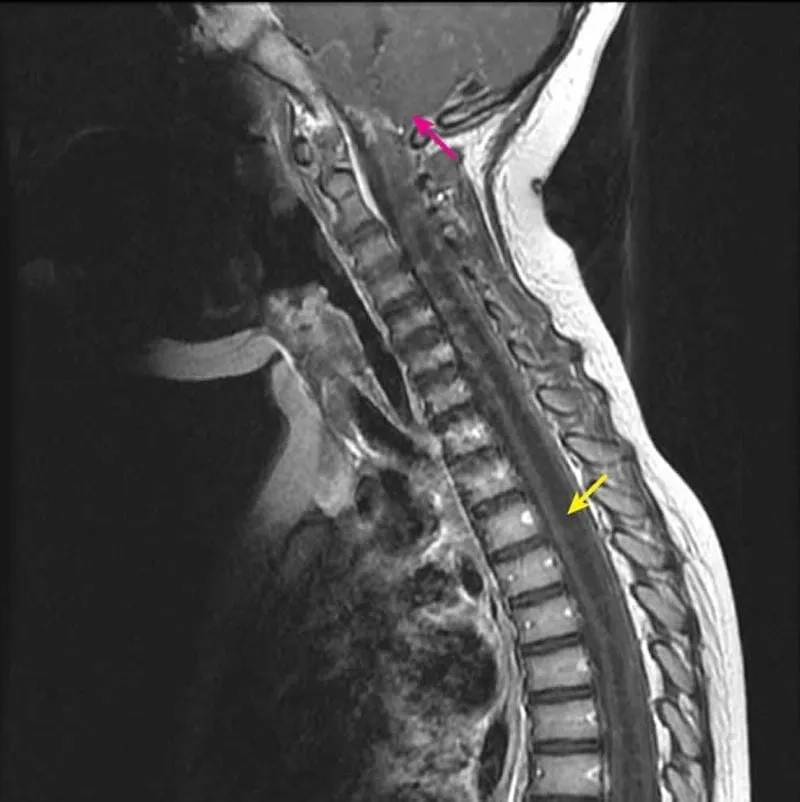

A before-and-after MRI following syringomyelia treatment